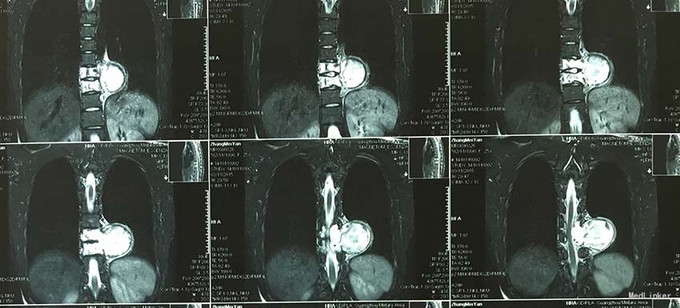

查体:脊柱外观无明显畸形,颈椎活动度正常,胸背部可见纵向长约15cm切口,皮肤钉缝合,伤口愈合可,无红肿渗液。胸椎9-10体左侧棘突旁局部压痛(+)、叩击痛(-),压头试验阴性,双侧侧臂丛牵拉实验(-),双上肢肌张力、运动、感觉及反射无明显异常、躯体感觉无明显减退,双下肢髂腰肌、股四头肌、胫前肌肌力IV级,感觉正常,双下肢直腿抬高试验(-),双侧腱反射对称略活跃,双侧Hoffman征(-),双侧Babinski征(-),双侧髌阵挛(-),踝阵挛(-)。 辅助检查:2015-11外院胸椎MRI检查发现T9-10节段椎体肿瘤并椎旁软组织肿块形成,肿块突入胸腔占位

诊断:胸椎椎体肿瘤(T9-10) 治疗:先于外院行1期后路椎弓根钉固定融合手术,然后转入我院行介入下术前椎体节段血管栓塞手术,第二天行经左侧胸腔入路椎体肿瘤病灶刮除并钛网植骨植入重建手术。术后恢复满意。复查MRI显示肿瘤病灶基本完全切除。